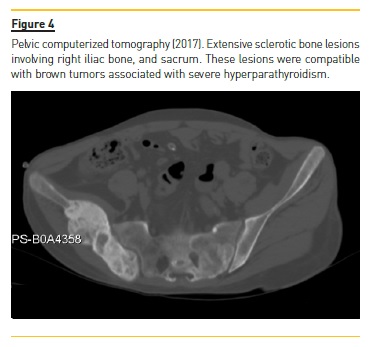

Four years later (2017), asymptomatic bone tumefactions of the knees were observed and imagiological re-evaluation was performed (Fig. 3 and 4), revealing expansion and esclerosis of previous lesions involving right iliac bone, distal femurs and right proximal tibia, as well as a new sacrum lesion. Bone scintigraphy confirmed hypermetabolic lesions and a subtotal parathyroidectomy was then performed.